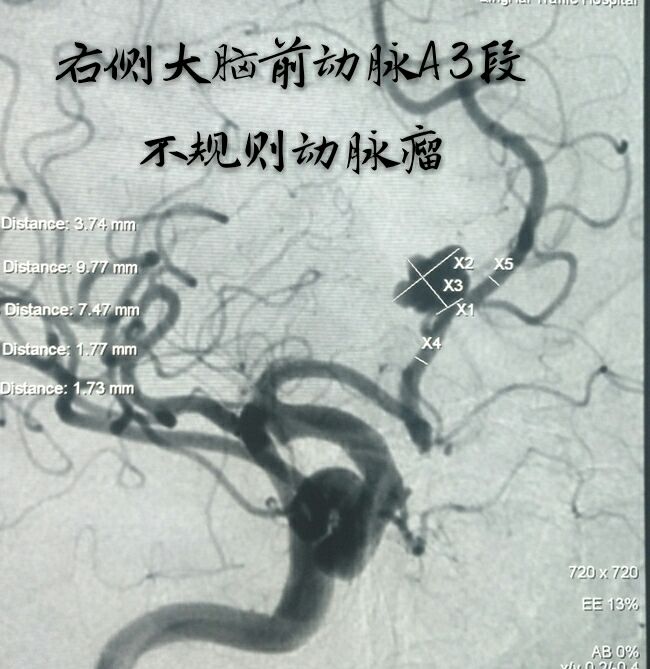

病例八:老年女性,间断性头痛、头晕1年,DSA发现右侧大脑前动脉A3段动脉瘤,形态不规则,宽颈

支架辅助下动脉瘤致密栓塞,难点:动脉瘤位置较远,通路迂曲,支撑导管不稳定